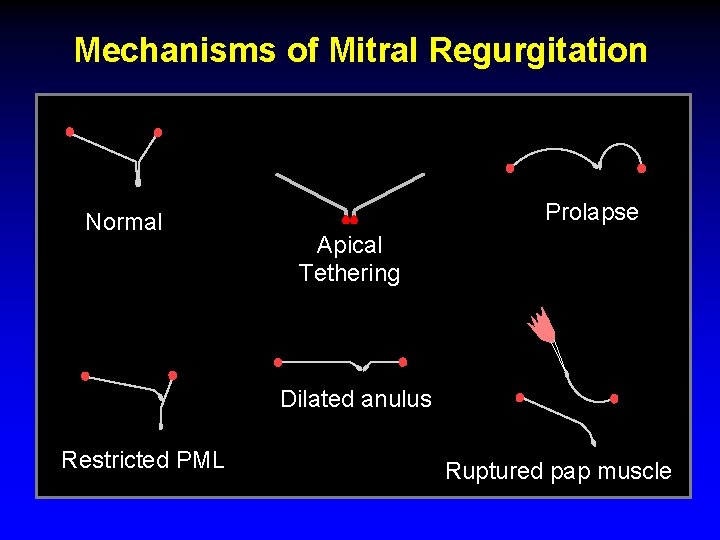

Mechanisms of Mitral Regurgitation Normal Prolapse Apical Tethering Dilated anulus Restricted PML Ruptured pap muscle